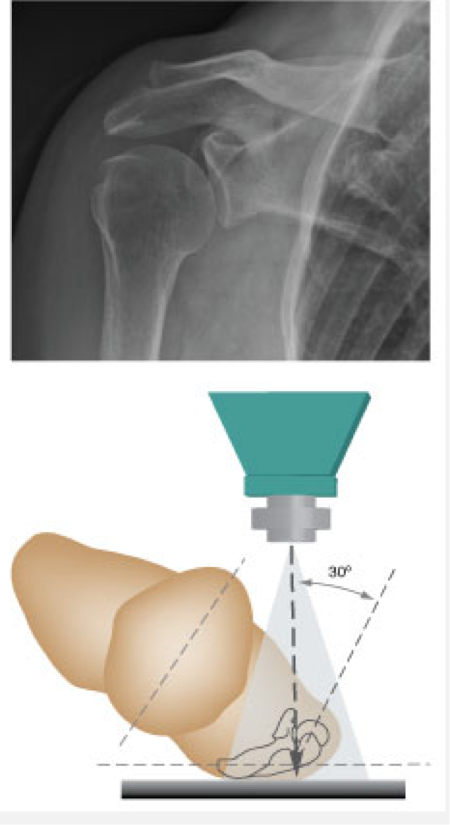

Oblique

Rotated view. this is left lateral oblique. Useful for shoulder joint dislocation or fractures

Grashey view

Oblique shoulder